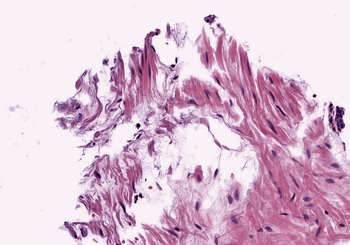

4.1 Quality of Color Normalization

A qualitative and quantitative comparison of the SPCN algorithm with other color normalization techniques is described in Vahadane et al. (2016), and justifies its choice as a starting point in this work. In Figure 2, we compare the performance of the original SPCN to our improved version on three challenging examples of source images taken from TCGA. On Image (a), the original SPCN exhibits swapping of stain color basis due to the presence of significant blue components in both stains. Our proposed improvement to compare the difference of red and blue components avoids this error. Image (b) illustrates that in cases where one stain dominates, SPCN can lead to a color tint in the intermediate whitespace. Our algorithm avoids this by estimating a channel-wise maximum pixel intensity. Image (c) shows an image with a significant background portion, which leads to a strong tinge in the background after normalization in an extreme case, which is also handled well in our results by estimating the maximum intensity for each channel separately.